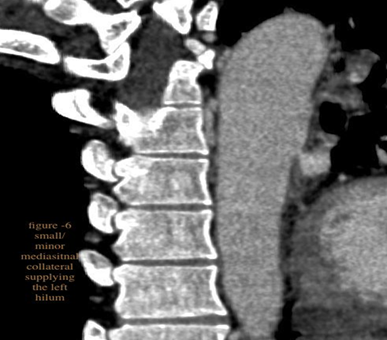

Persistent truncus arteriosus is an uncommon complex congenital heart disease. Without surgical intervention, the prognosis is not good. Very few untreated cases of truncus arteriosus survive to maturity. We report an exceptional case of uncorrected truncus arteriosus surviving into adulthood of type a3 variant -van praagh classification as a 26-year-old male who had well tolerated dyspnea since birth. Our patient showed a single(right) pulmonary artery arising from the common arterial trunk supplying the right lung and absent main and left pulmonary artery with collateral supply to the left lung consistent with the truncus arteriosus type a3-van praagh classification